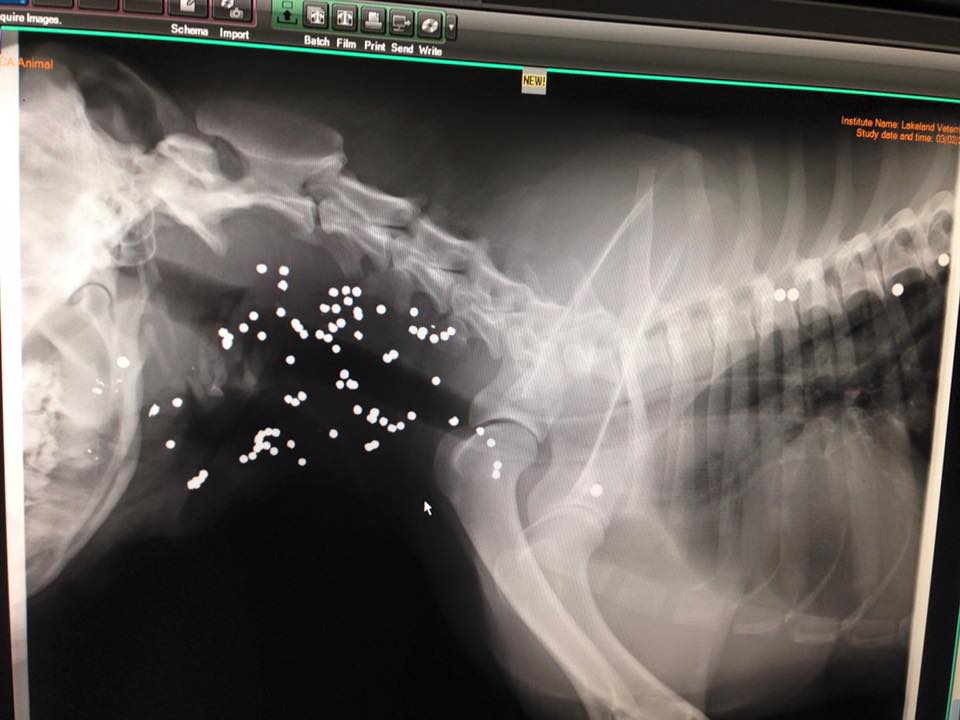

A shepherd cross is recovering from a shotgun wound to the face and shoulder. The dog, which has been named Remington, was found near Glaslyn, Sask. and was brought to the Battleford’s Humane Society on Wednesday.

Dr. Leo Perlinger, a vet at Lakeland Veterinary Service in North Battleford, is caring for the dog. He says despite Remington’s extensive wounds the dog arrived in surprisingly good spirits. Perlinger believes that because of infection, the year-and-a-half-old dog must have been on his own for a several days before being found.